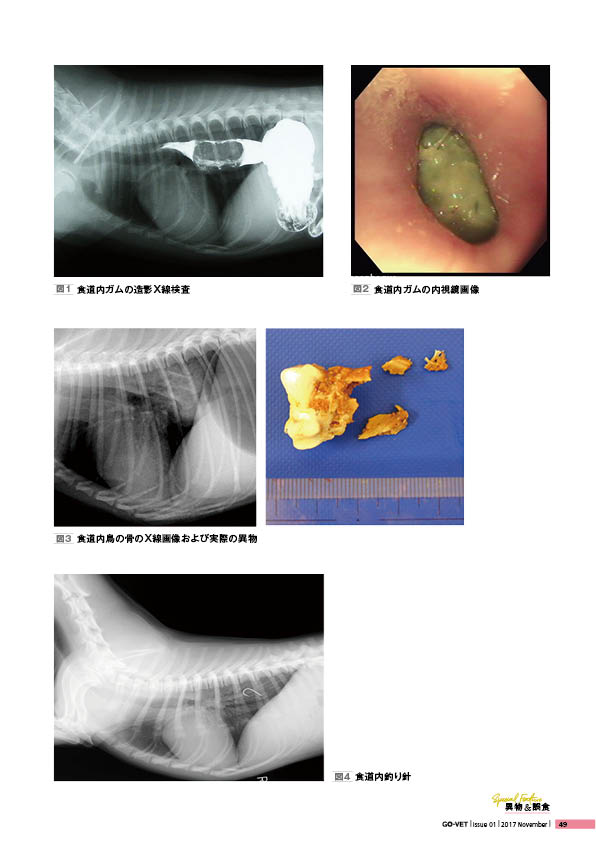

小動物外科専門誌 SURGEON 126号(2017/11月号) [雑誌] SURGEON。雑誌 GO-VET 2017年11月号「創刊号」 No.1 | 雑誌 | 株式会社学窓社。SURGEON 160 Vol.27 No.4 2023 裏表紙 に『QIX Muscle & Joint。

小動物外科専門誌SURGEON126号(2017/11月号)

• 雑誌 GO-VET 2017年11月号「創刊号」 No.1 | 雑誌 | 株式会社学窓社